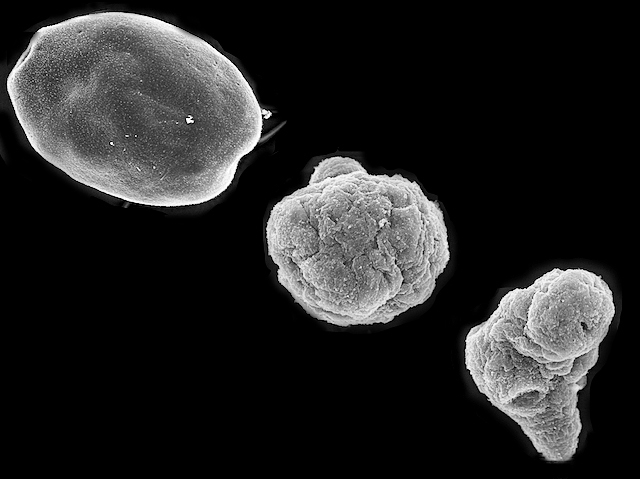

These amorphous blobs, many times smaller than a speck of dust, cause over 1000 deaths each year, affect over a million people around the world at any one time, and wreak $3 billion dollars’ damage annually. They’re the larval stage of tapeworm Echinococcus granulosus – the parasite that causes cystic echinococcosis. Livestock and dogs most frequently fall prey to cystic echinococcosis, but it also affects humans, for whom prolonged uncomfortable drug therapy and surgery are often the only options. A study exploring new potential treatments tested glibenclamide – a drug currently used to treat diabetes. It found that the parasite larvae faltered in the presence of glibenclamide – illustrated by the shrivelled structure of the struggling parasites exposed to the drug (centre and right) compared to the untreated larva (top left). The treatment also reduced the size of cysts in infected mice, raising real hopes for this new approach.